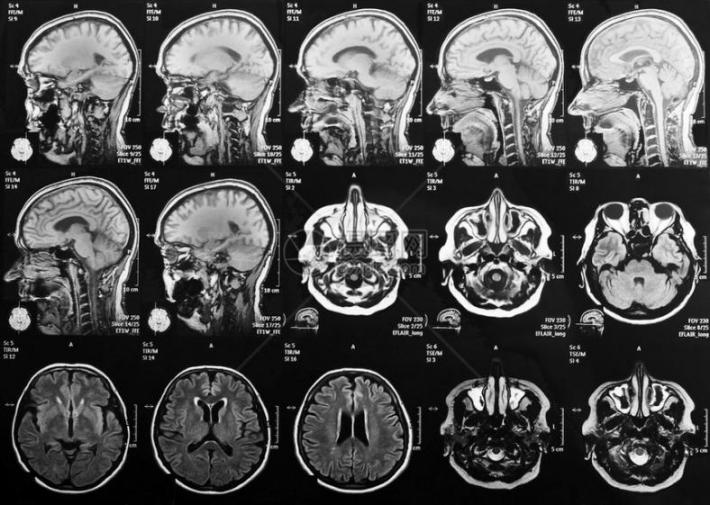

探密脑科学⑤|磁共振如何带我们看见大脑的思考?

我们每天都在思考,但思考时大脑里发生了什么?利用磁共振成像设备(MRI),科学家们就如同操作一台超级‘大脑摄像机’,使得我们能‘看见’大脑的活动。

磁共振成像(MRI)就像是一种用强磁场给大脑照片的技术。人体内富含氢原子,这些氢原子在强磁场里会排好队,像小磁铁一样。这时,机器会发射出一种特殊的信号,短暂地“推”或“打扰”一下这些小磁针,让它们的队形暂时乱了。等这个“信号”停止后,被推乱的小磁针又会努力转回原来的方向。就在它们转回去的过程中,自己也会发出微弱的信号。机器捕捉到这些返回的信号,经过处理,就变成了我们看到的大脑清晰图像。

人脑在执行特定任务(如看图片、做数学题、回忆事情)时,与该任务相关的脑区可能会被激活。 科学家们借助fMRI可获得人体大脑在这些任务状态下的图像数据,通过对比不同任务下的大脑激活图,就能知道哪些脑区参与了特定类型的思考或感知。比如,观看人脸时,与面孔识别相关的‘梭状回面孔区’可能会被激活。

通过探测不同任务状态下大脑的血氧变化,磁共振技术得以标识忙碌的脑区。这为研究大脑工作机制,理解大脑的各种功能提供了强大工具。